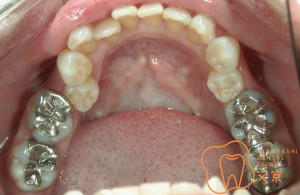

■銀歯の取り替え